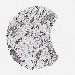

BRCA TCGA BRCA VALIDATION PROTEIN EXPRESSION

ANTIBODIES

AND

VALIDATION